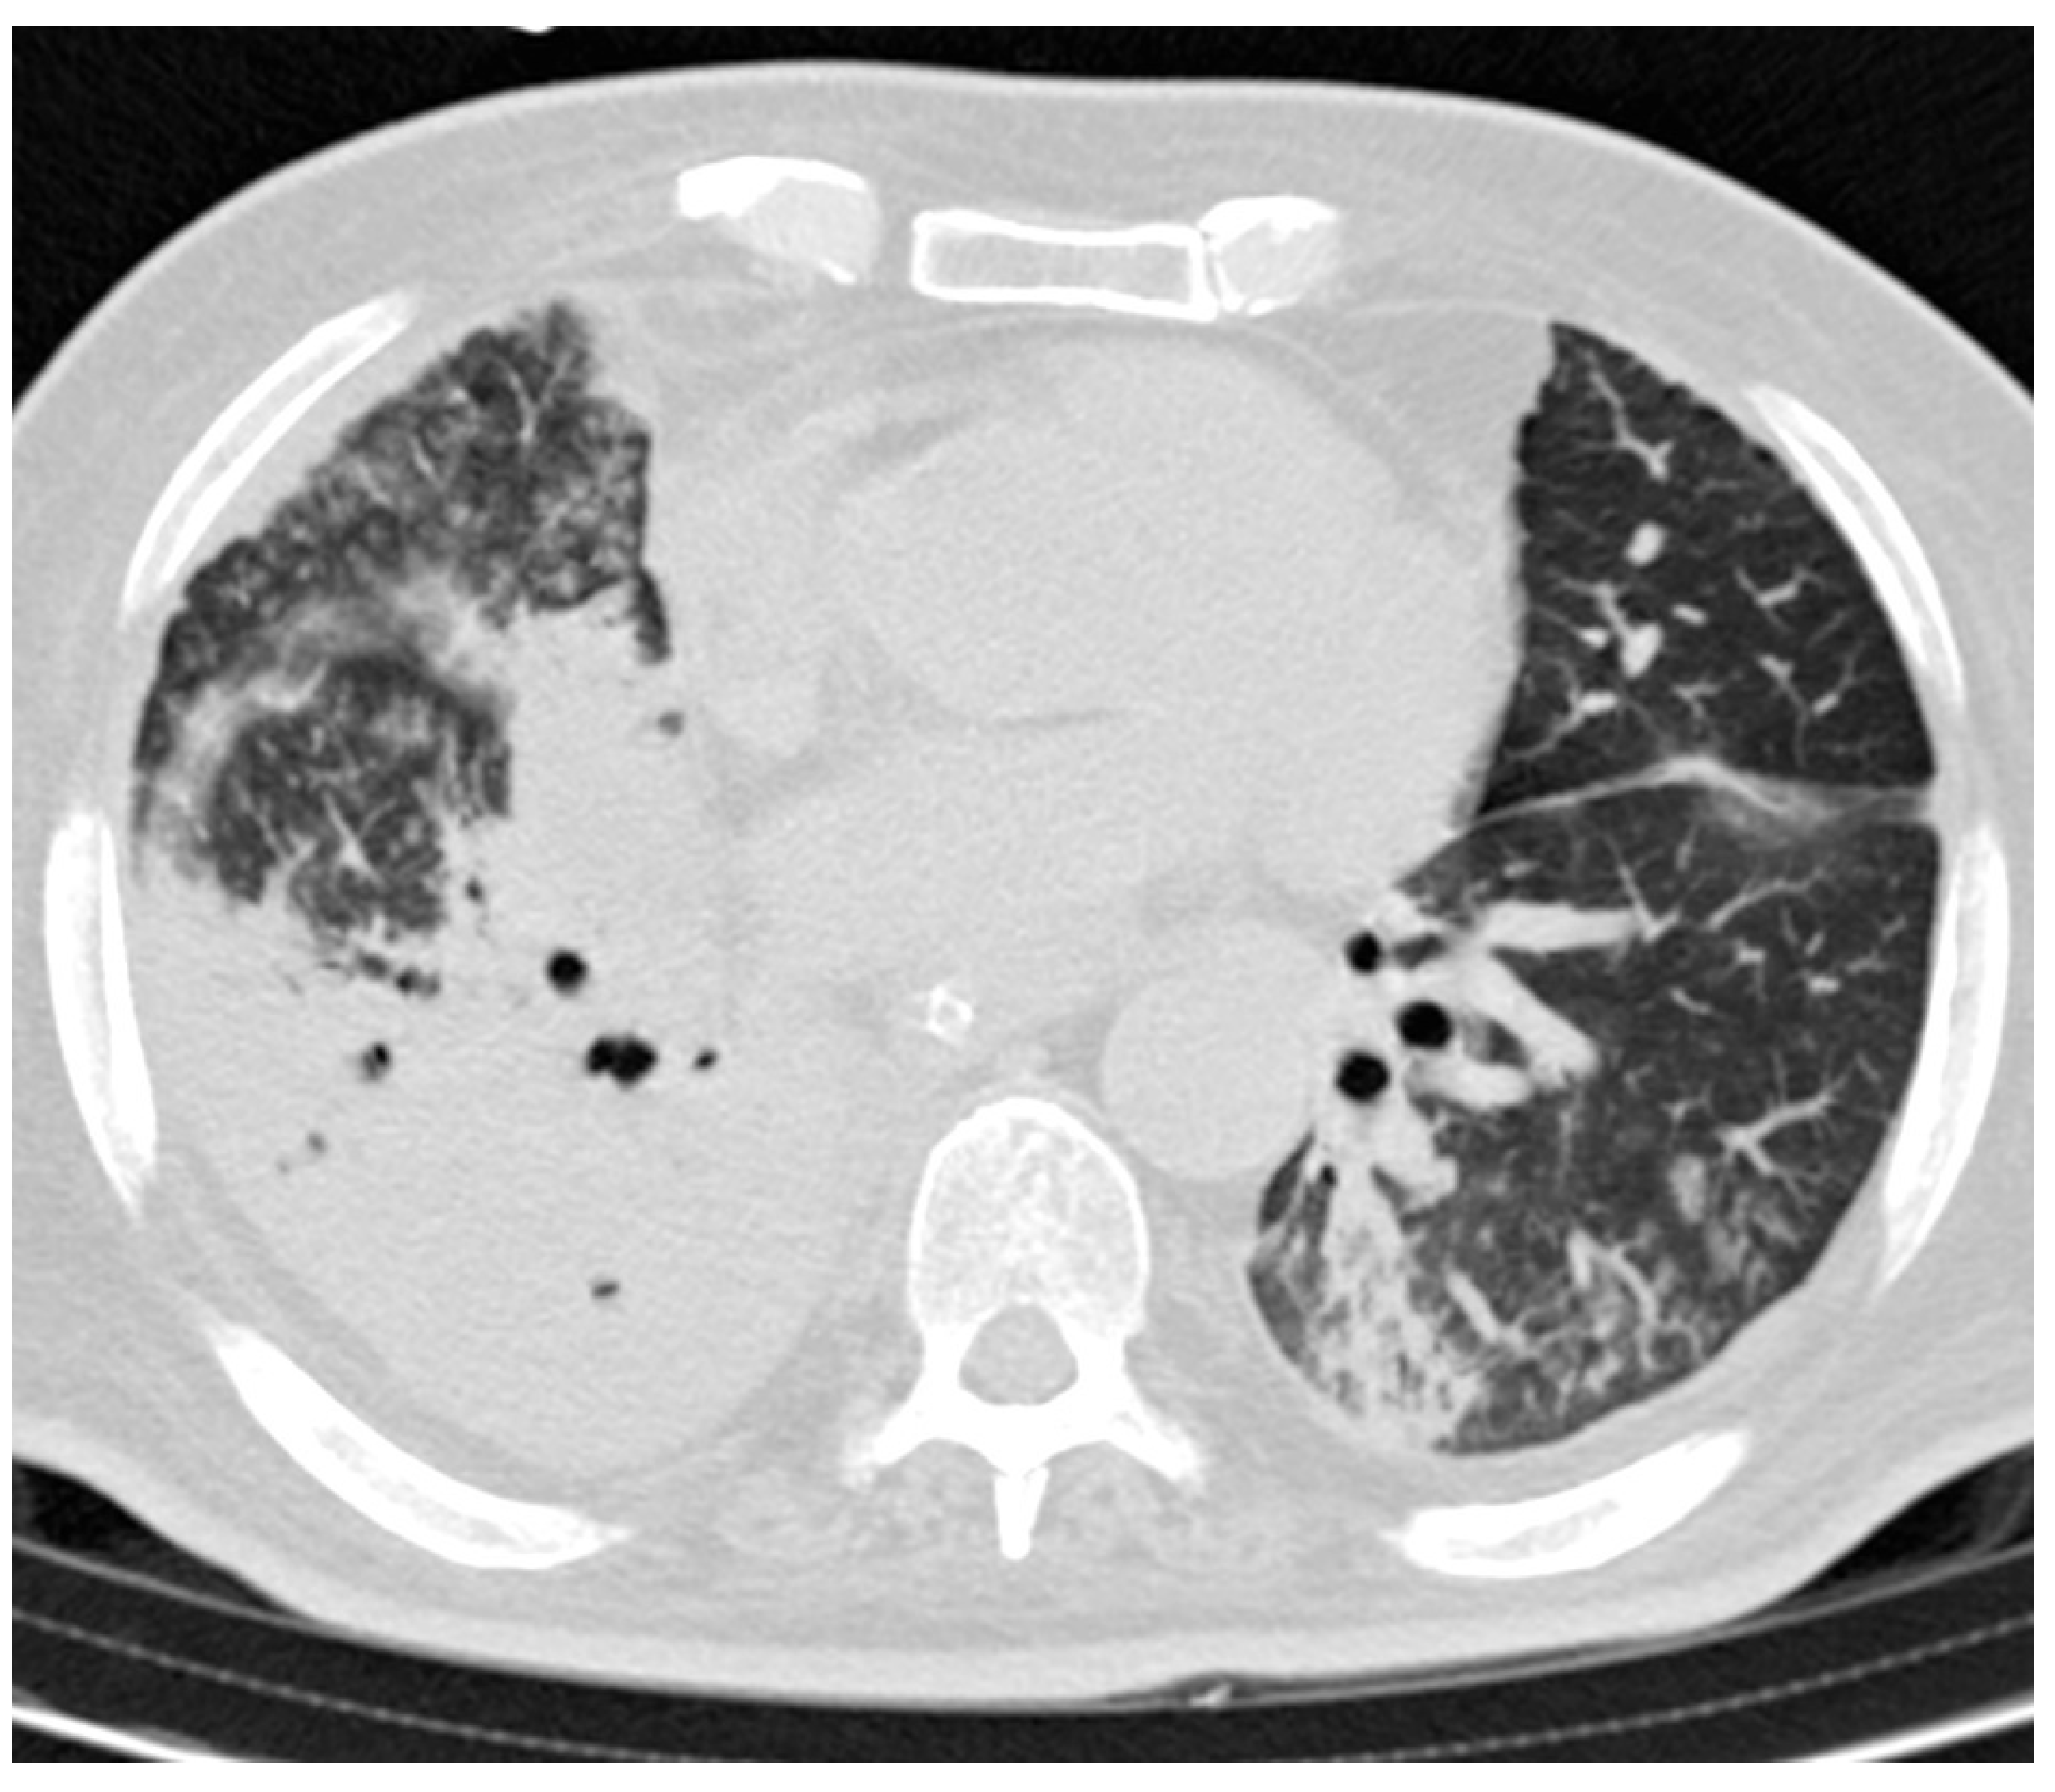

2. Methods and Materials

3.3. CT Findings and Disease Distribution

3.4. Statistical Tests